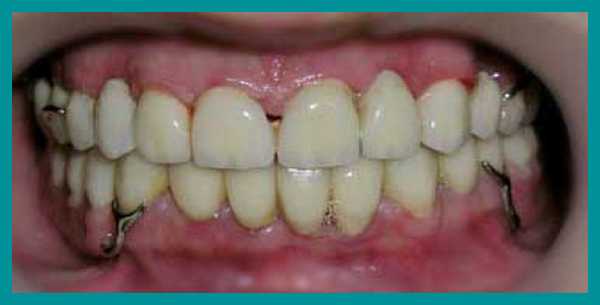

После фиксации металлокерамических коронок на постоянный цемент, коррекции и установки бюгельных протезов на кламмерах, пациент получил рекомендации по уходу за зубными протезами и проведению личной гигиены полости рта. План лечения был выполнен. Рекомендовано профилактическое посещение стоматолога каждые четыре месяца.

Итог лечения

От начала лечения и до его завершения прошло больше года. В итоге пациент получил эстетичные и очень функциональные зубы, исчез психологический дискомфорт. Одновременно была решена проблема неправильного прикуса, восстановлена работа височно-челюстного сустава.